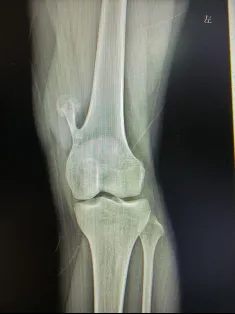

(影像说明:左膝关节正位X线片,左侧股骨远端可见典型带蒂骨性突起,背离关节面生长,骨皮质、骨髓腔与宿主骨相延续,这是骨软骨瘤特有的影像学表现)

从片子上可以清晰看到:女孩左侧大腿下端靠近膝盖处,骨头向外长出了一处明显的骨性凸起。